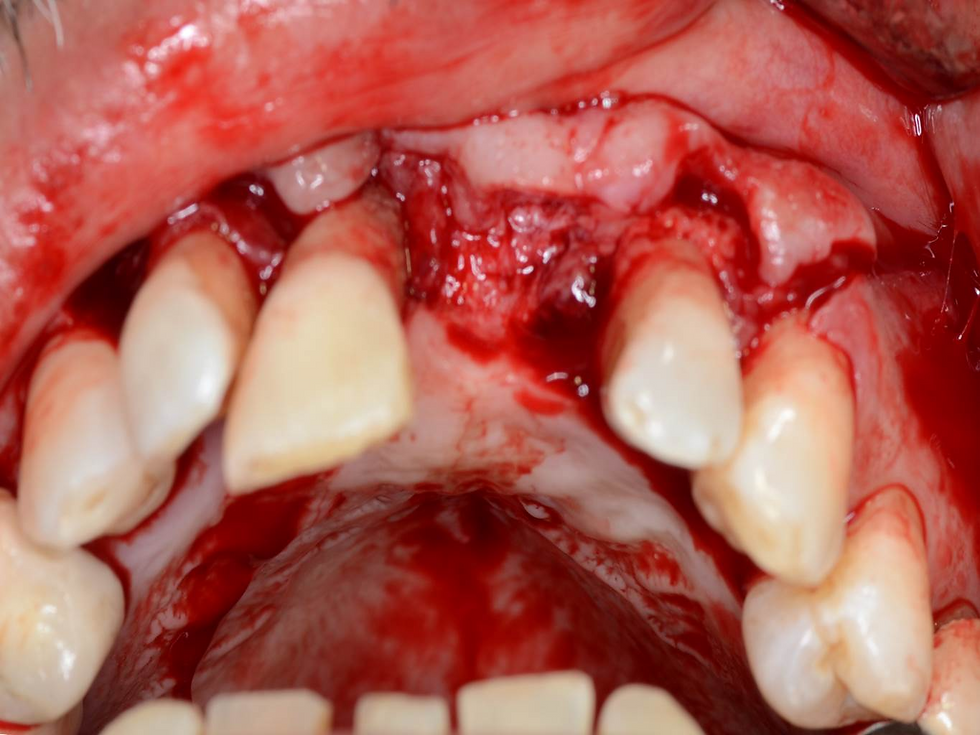

- Initial situation with a high lip position (left), Intra oral view of the area (right)

- Missing tooth on #21

- Periodontal disease